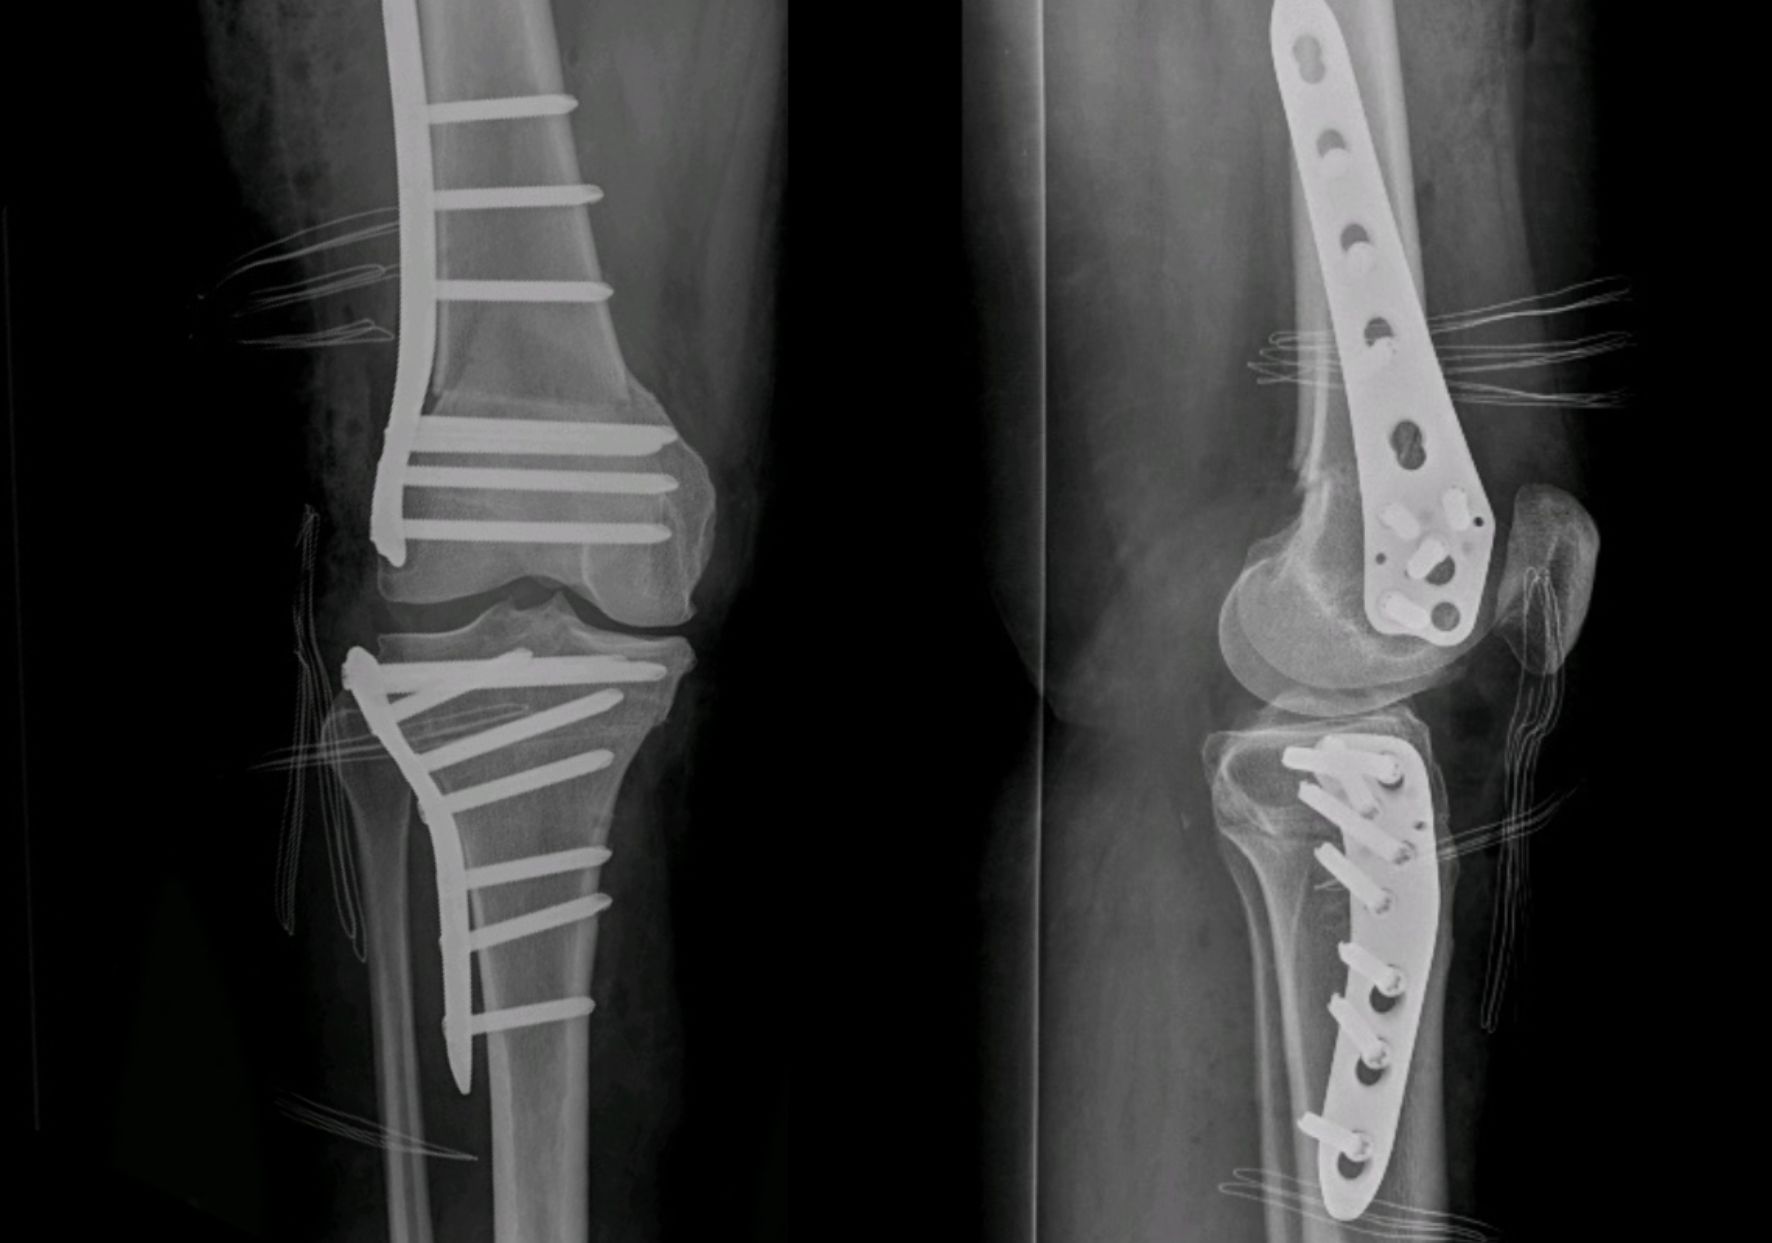

Fixation Method

Once the derotation is achieved, the tibia must be fixed in the new position. This can be done with specifically designed plates and screws, or with staples. This decision will be left to surgeon's preference. Plating has the advantage of more theoretical stability. However, its drawbacks include losing some degree of correction while plating (longer time screwing), longer procedure time, need of hardware removal, longer incision, and a higher cost. It is likely more suitable for tridimensional osteotomies (correction of valgus and torsion) where a more rigid fixation is required (Figure 12).

In isolated supratuberositary osteotomies, lateral compression staples are usually enough for a correct fixation. It reduces the operating time and maintains the correction of the torsion quickly when obtained, while also being less irritating for soft tissues than a plate. The use of two staples is recommended. The first staple is inserted from lateral to medial (Figure 13), and the second staple can be inserted in the same manner or, if possible, from anterior to posterior, perpendicular to the other to prevent loss of rotation (Figure 14). In some cases of medial opening after fixation, a further staple can be added on the medial side with a small incision (Figure 15). However, this is not advised as the medial staples can be highly irritating.